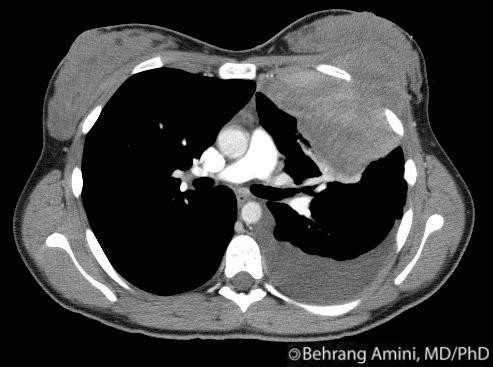

43yo F with SLE presents with dyspnea

Pericardial Effusion

cardiac shadow is enlarged but the pulmonary vessels are not dilated –> suspect a pericardial effusion.

azygous vein and SVC may be dilated, reflecting the elevated central venous pressure necessary to maintain right ventricular filling.

mediastinal interface over the left hilum in the absence of enlargement of the pulmonary arteries should also alert you to possibility of a pericardial effusion (fluid accumulating in a pericardial recess) because an enlarged cardiac chamber, such as the left atrial appendage, will not produce an interface this high along the left cardiac border.